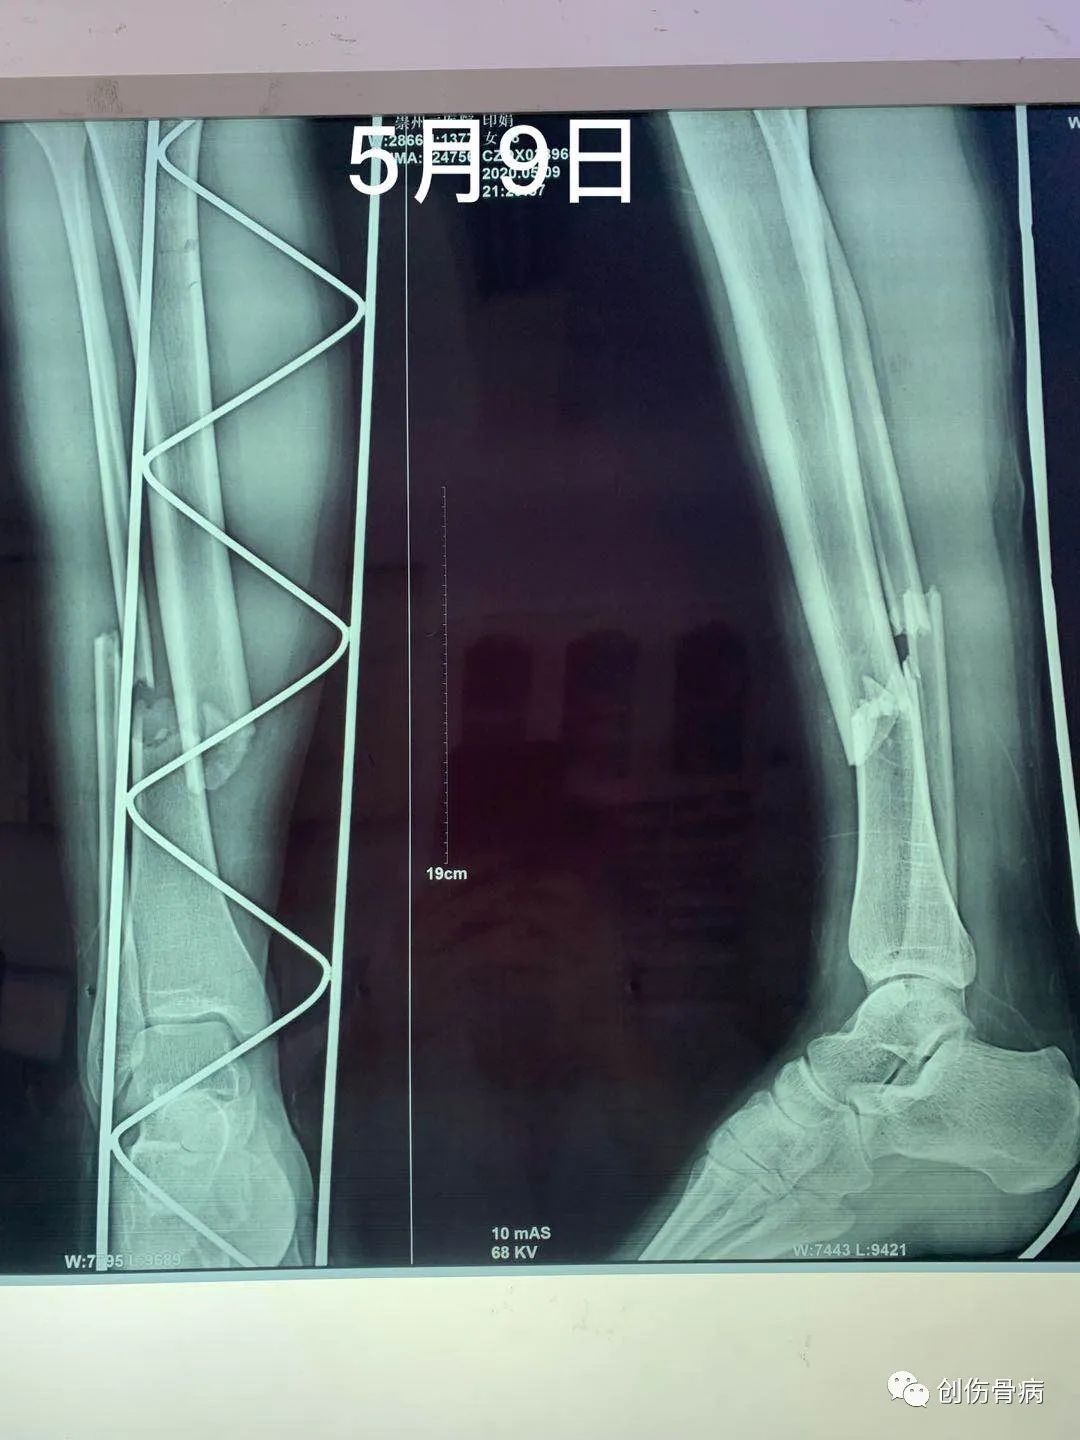

都说车祸无情,但是创伤后的并发症也仍然无情。2020年5月9日21时55分我科室接收一名18岁外伤小妹妹,当天晚上小妹妹跟爸爸妈妈路边漫步被一汽车撞倒受伤,送至我院时就是一单纯右胫腓骨下段粉碎性骨折伴头皮裂伤,入院行右小腿DR及胸部CT示:2020年5月12日14时左右,小妹妹突然出现呼吸困难、烦躁不安,氧饱和度40-50%,家属诉小女孩昨日夜间有偷偷咳嗽的表现,当班医生一看就考虑脂肪栓塞立即给与安排行胸部CT示:

肺部情况稳定后于2020年5月28日行右胫腓骨下段粉碎性骨折手术治疗